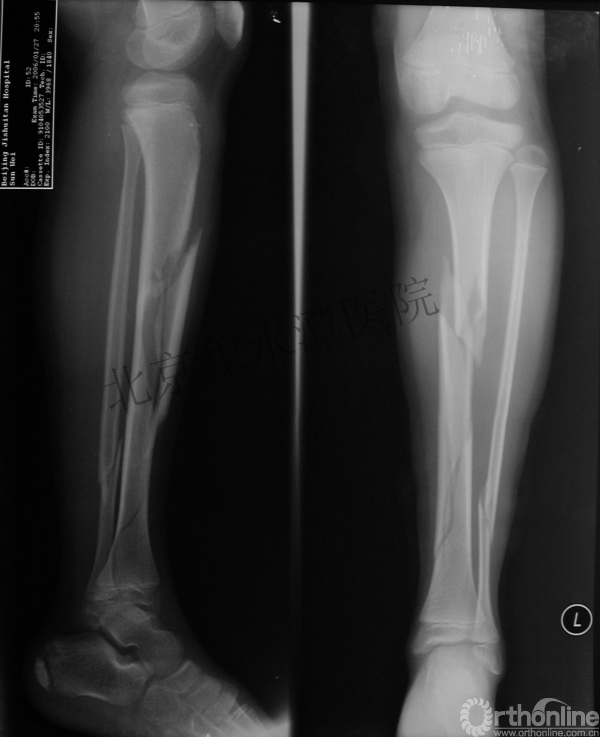

男孩、9岁,滑雪受伤,胫腓骨螺旋形骨折(粉碎性)

这个病例郭教授在积水潭医院骨科高研班时多次讲到,也在互动交流中惊人地看到,了解到现实之令人难以想象!

手法整复,石膏制动!

整复后7天

儿童具备强大的愈合潜力,同样也有极强的塑形能力